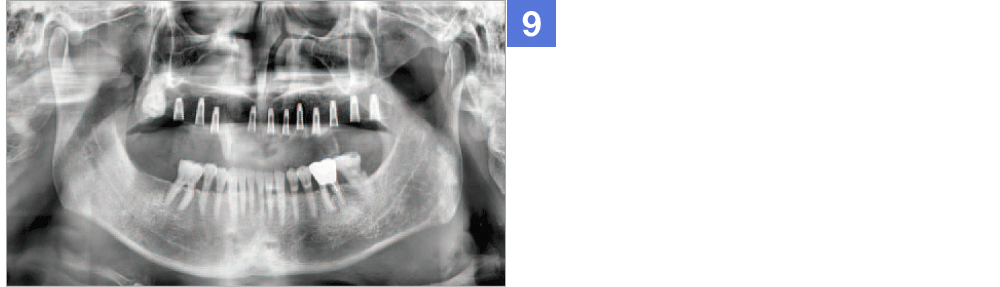

Through virtual operation procedure though 3D computer, DIO NAVI system decreases danger of implant surgery by checking patient's bone tissue and nerve position for planning the optimal surgery procedure and making customized surgical guide.

DIO NAVI surgery is planned after 3D computer simulation surgery is done, and it is up-to-date digital navigation implant surgery done with minimal incision and little pain in short time.

Not only the mock implant surgery plan that considered the occlusion and stress dispersion, but 3D simulation that can be used as a counseling material for the patient is provided. The doctor can establish a satisfactory treatment plan and with a provided surgical guide, He can operate a safe and accurate procedure.

Through implant planning that considered occlusion and stress dispersion, DIO NAVI Digital Implant System increases the accuracy of the implant treatment and enabled 3D simulation that is used for patient counsel purposes.